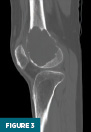

CT of the right knee without IV contrast showed a heterogenous mass within the lateral aspect of the distal femur centered in the metaphysis and extending into the epiphysis. This mass measured 7.1 cm x 6.7 cm x 6.1 cm. There was associated cortical thinning, heterogenous cortical disruption (most prominent along the supralateral aspect), and endosteal scalloping along the margins (Figures 3–5).

Radiographs, CT, and MRI all contribute to establishing the diagnosis. Radiographically, GCTB lesions are typically lytic and eccentric, arising in the metaphysis of long bones and extending into the epiphysis, often to the subarticular bone. Most lesions are geographic with a narrow transition zone. A sclerotic margin is usually absent, although up to 5% of cases demonstrate sclerosis. CT is useful for evaluating cortical thinning and breakthrough, as illustrated in this case. On MRI, lesions typically demonstrate low to intermediate signal intensity on T1-weighted images and demonstrate inhomogeneous signal intensity on T2/STIR sequences, due to hemorrhage or collagen content. Postcontrast images reveal heterogeneous enhancement. These features were evident in our patient’s imaging and were central to guiding the diagnosis.